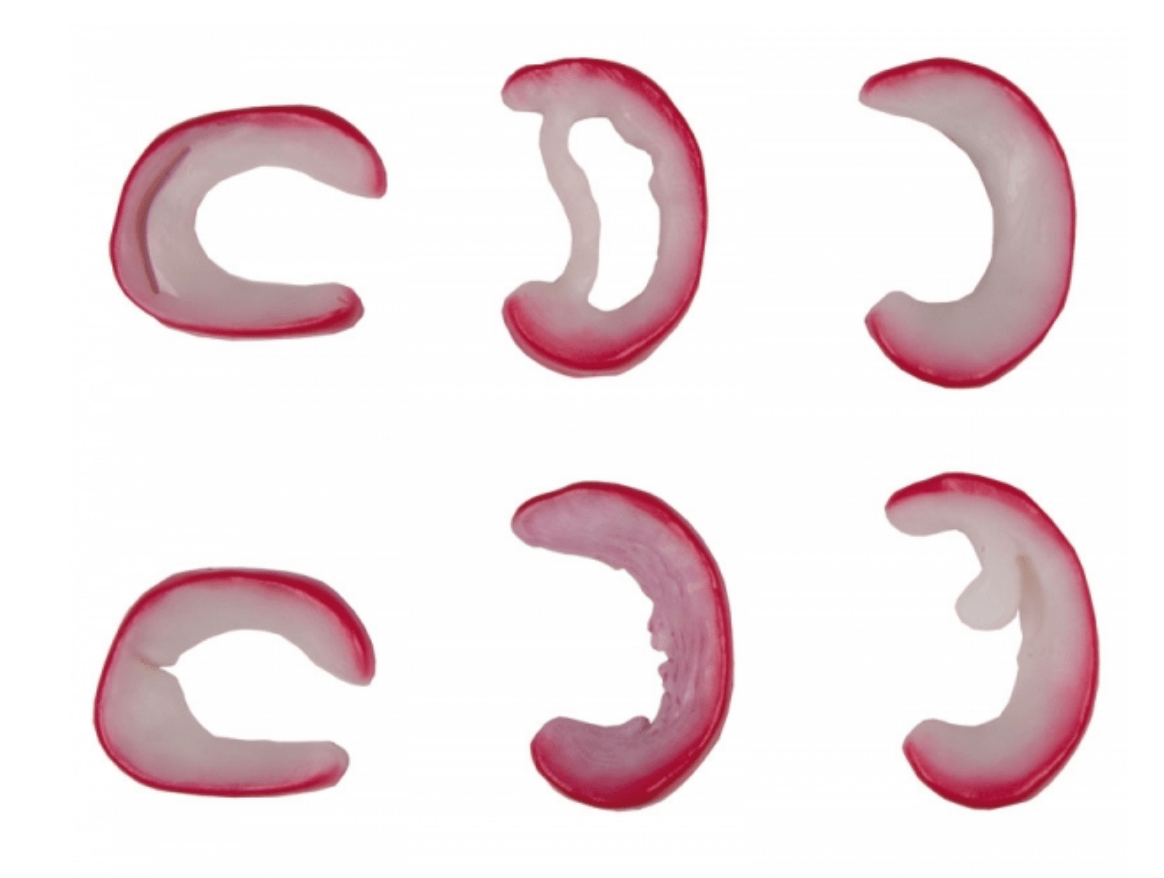

Salg af anatomiske modeller er det bærende element i eAnatomi, selvom vi også bruger mange ressourcer på at udvikle vores egne anatomiske materialer som fx plakater. Anatomiske modeller anvendes til forskellige formål og kan både vise afgrænset væv, organer samt organsystemer. Søger du en simpel model af knoglevæv eller måske en avanceret torso-model baseret på MRI teknologi, kan du finde det hele på eanatomi.com.